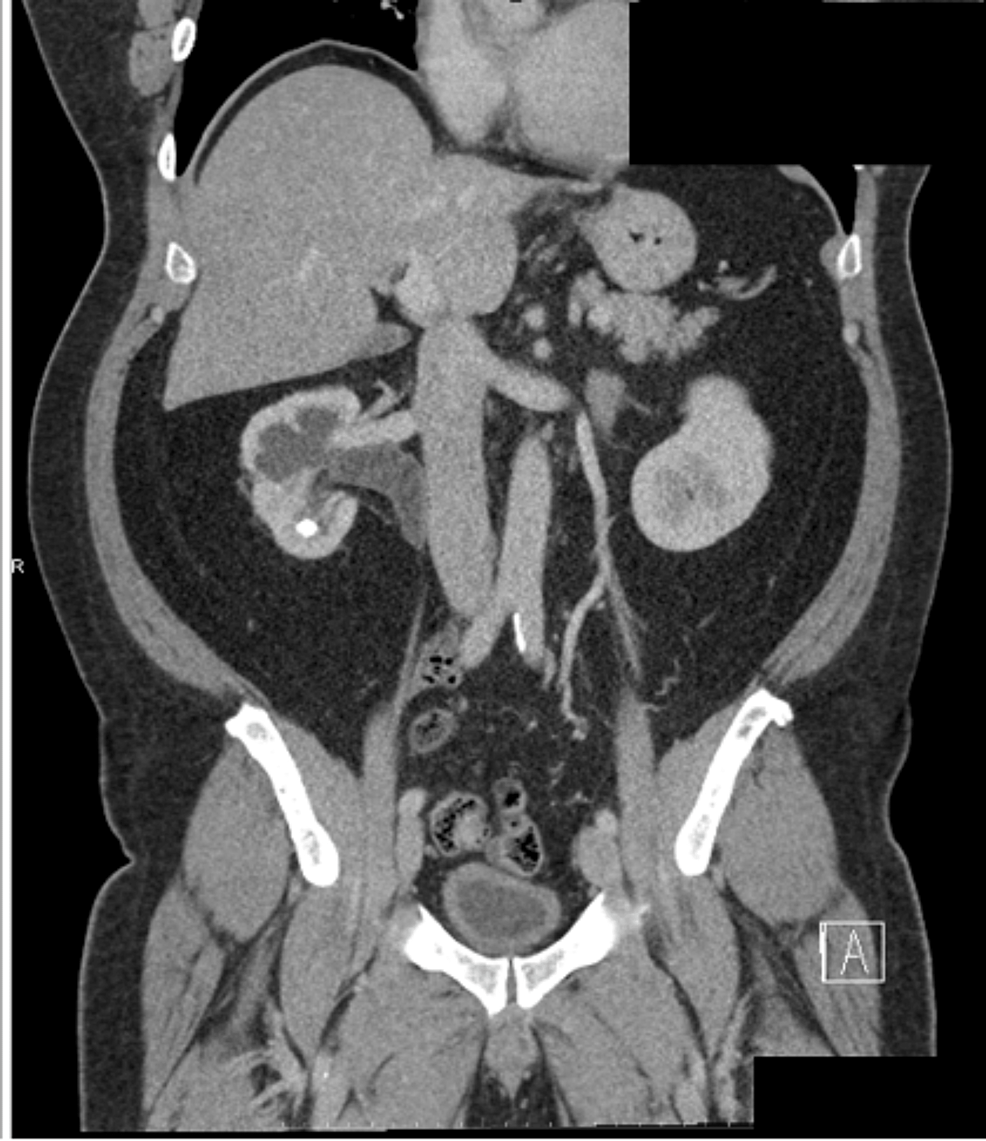

Figure 4 from Discovery of Primary Hyperparathyroidism in a Patient Radiopaque Nephrolithiasis In this article, we review the standard of care for imaging of nephrolithiasis as well as new technology. urolithiasis refers to the presence of calculi anywhere along the course of the urinary tracts. kidney stone disease (nephrolithiasis) is a common problem in primary care practice. plain radiography provides an acceptable assessment of stone activity in most patients. Radiopaque Nephrolithiasis.